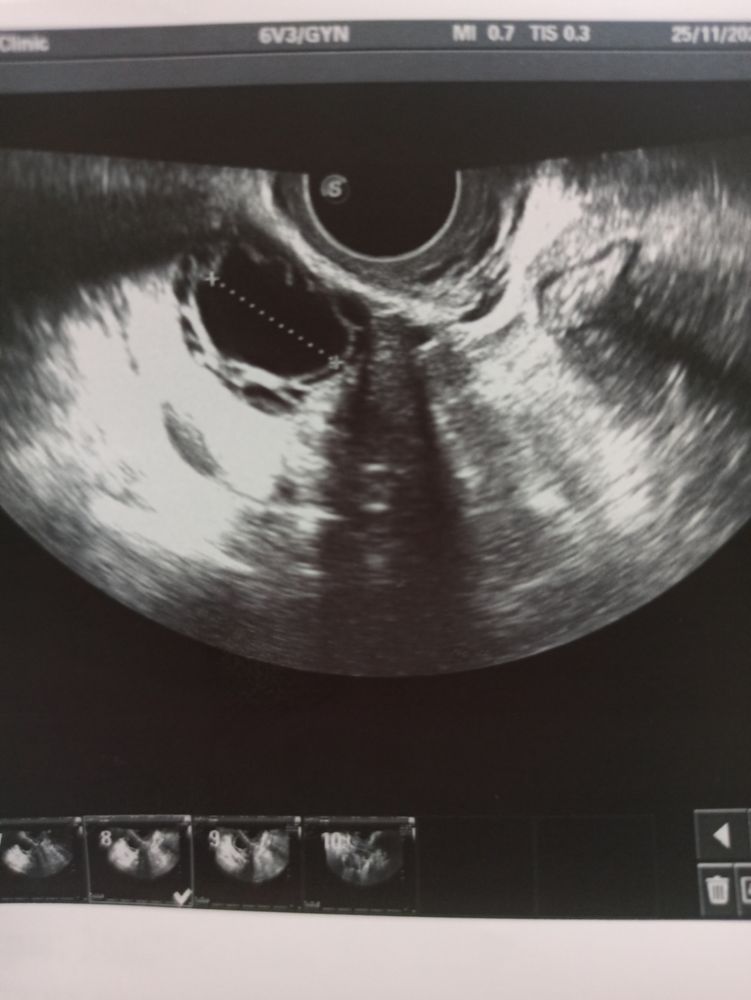

Фолликулометрия, ЖТ или фолликул?

Но судя по картинке это фолликул

Мария , вот свои УЗИ скину. Понятно сразу фолликул он как бы чёрный, а ЖТ оно как образование с неровными контурами Изображение

Мария , да не за что . У Вас по-моему на фото как раз момент, что вот вот овуляция будет .

У вас это доминантный фолликул и по нему видно что скоро овуляция он дряхлый! У меня так было с дочкой поймала её еще когда из фолликула выходила😂 желаю вам скорейшей беременности 😽

Вижу ДФ и по ходу просто лопался уже

Мария , момент овуляции видимо поймали